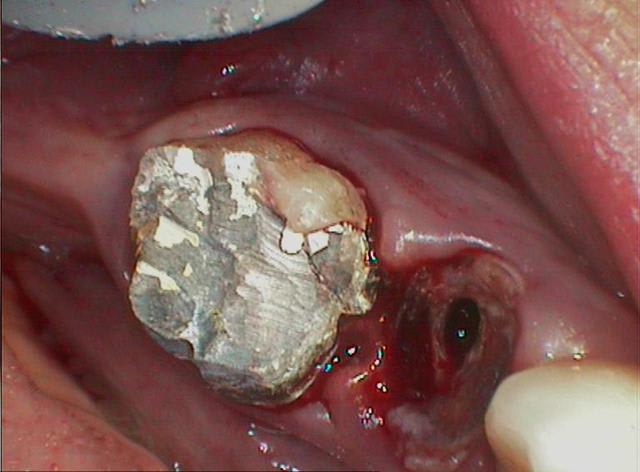

que faire ? je pense que la fistule vest vient de la prémolaire...

tenez ! cadeau

c'est le même praticien

vous noterez la position du pivot

et l'optimisme du praticien qui l'a posé dans une dent vivante

"coup de chance" ou "manque de pot" c'est à coté

je ne sais ce qui valait mieux